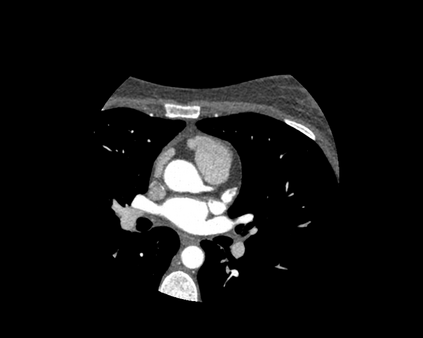

The standard non-invasive imaging technique used to assess the severity and extent of Coronary Artery Disease (CAD) is Coronary Computed Tomography Angiography (CCTA). However, manual grading of each patient's CCTA according to the CAD-Reporting and Data System (CAD-RADS) scoring is time-consuming and operator-dependent, especially in borderline cases. This work proposes a fully automated, and visually explainable, deep learning pipeline to be used as a decision support system for the CAD screening procedure. The pipeline performs two classification tasks: firstly, identifying patients who require further clinical investigations and secondly, classifying patients into subgroups based on the degree of stenosis, according to commonly used CAD-RADS thresholds. The pipeline pre-processes multiplanar projections of the coronary arteries, extracted from the original CCTAs, and classifies them using a fine-tuned Multi-Axis Vision Transformer architecture. With the aim of emulating the current clinical practice, the model is trained to assign a per-patient score by stacking the bi-dimensional longitudinal cross-sections of the three main coronary arteries along channel dimension. Furthermore, it generates visually interpretable maps to assess the reliability of the predictions. When run on a database of 1873 three-channel images of 253 patients collected at the Monzino Cardiology Center in Milan, the pipeline obtained an AUC of 0.87 and 0.93 for the two classification tasks, respectively. According to our knowledge, this is the first model trained to assign CAD-RADS scores learning solely from patient scores and not requiring finer imaging annotation steps that are not part of the clinical routine.